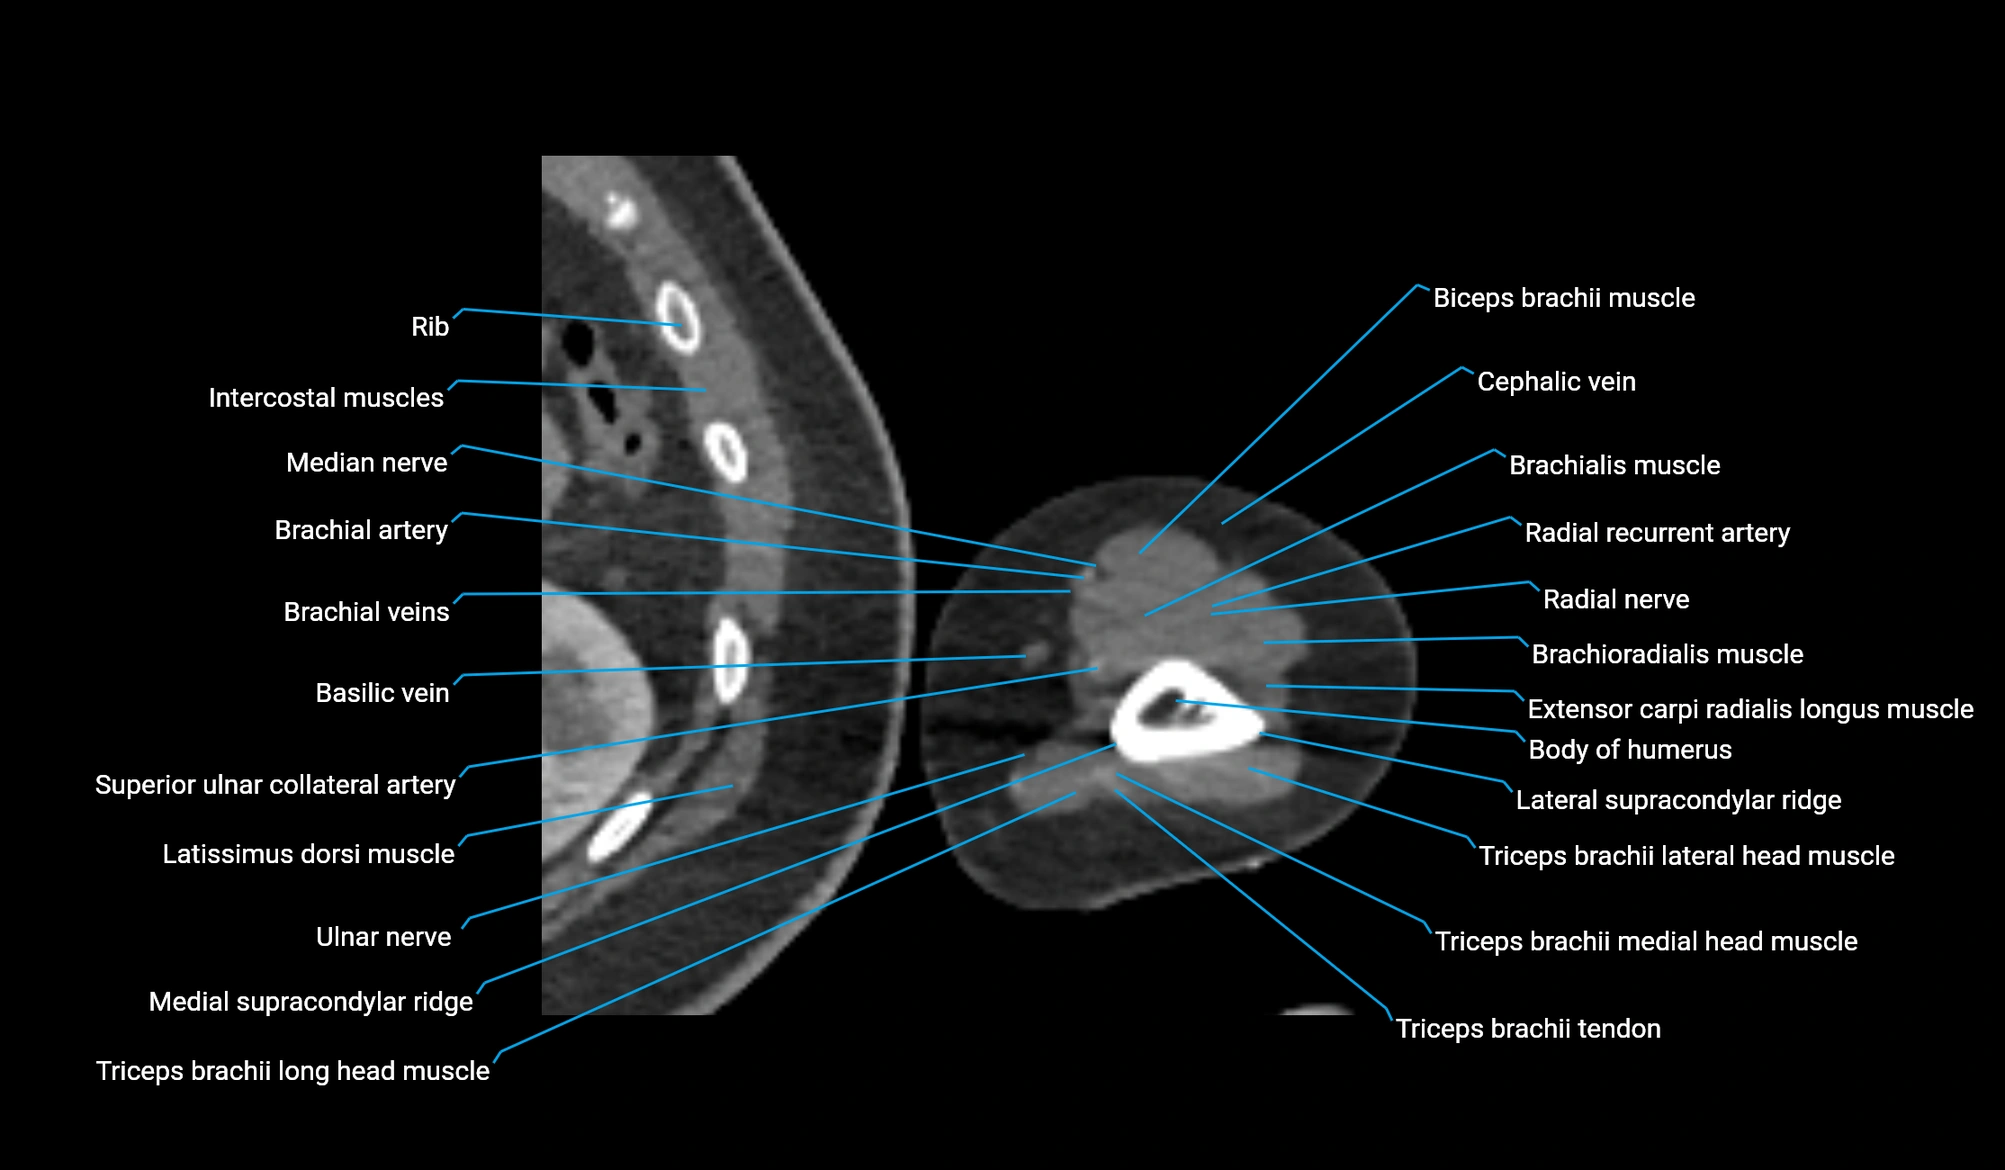

CT image